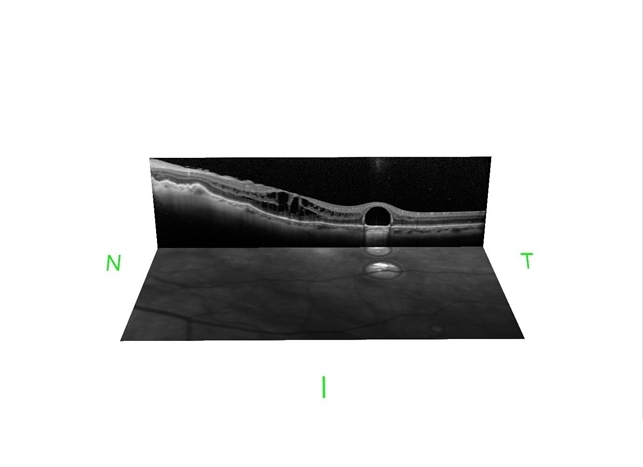

- macular edema, post-vitrectomy, retained perfluorocarbon

- Optical coherence tomography system

- SD-OCT and HRA from a 42-year-old patient after silicon oil removal. The image shows macular edema and retained perfluorcarbon.